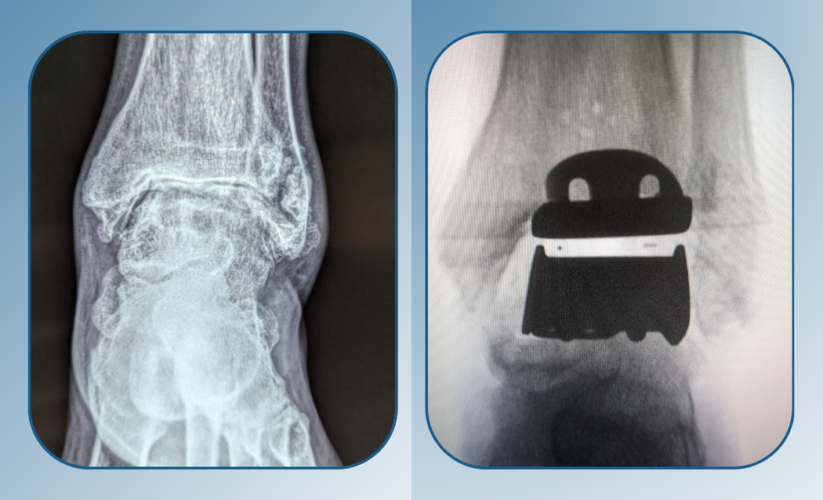

2. Charcot Foot Reconstruction

For patients developing collapsed or deformed feet due to neuropathy, reconstructive surgery restores stability and prevents long-term disability.